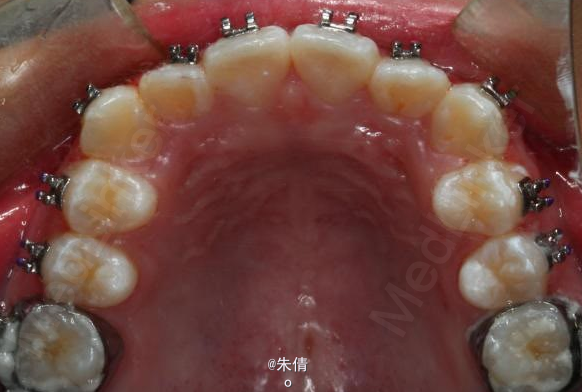

对于面型较好,拥挤度不大的病例,推磨牙向后不失为一种很好的方法,当然现在推磨牙后向的手段和方法很多,但是主要 是适应证的问题。我认为我们在做推磨牙向后,首先是考虑拥挤度,第二个要考虑的是现有的面型,第三点也是很重要的一点,是考虑牙弓后段拥挤度,Tweed-Merryfireld拥挤度的诊断方法将牙弓拥挤度分析分为三段,牙弓前段拥挤度,牙弓中段的拥挤度,以及牙弓后段的拥挤度。不管用什么方法或是手段推磨牙向后,一定不能将牙弓前端矛盾移到牙弓中段或是后段。今天给大家看一直面型,拥挤度不是很大推磨牙向后的病例。希望对大家能有所帮助。